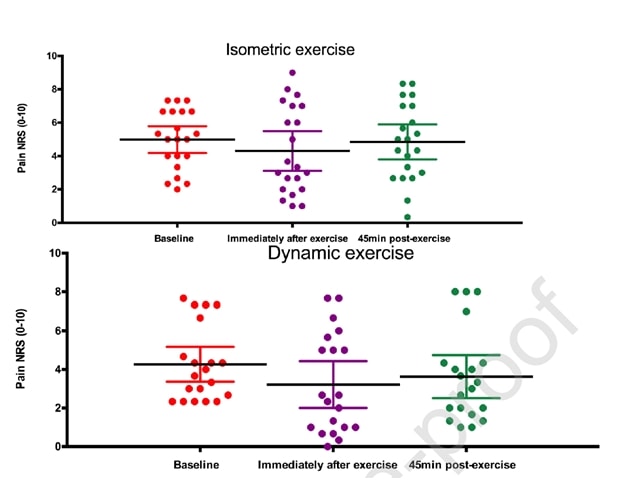

Rio et al. (2015) hanno avviato una tendenza quando hanno condotto uno studio cross-over su 6 giocatori di pallavolo con tendinopatia rotulea. I risultati sono stati sorprendenti: tutti i giocatori hanno registrato un'immediata diminuzione del dolore, passando da una media di 7/10 sull'NRS a 0, e solo uno dei 6 giocatori ha riportato un dolore residuo di 1 per almeno 45 minuti dopo le contrazioni isometriche. Il protocollo utilizzato era di 5 serie con 45 secondi di contrazione in una macchina per l'estensione delle gambe e uno sforzo pari al 70% dello sforzo volontario massimo. Hanno anche scoperto che l'isometria era in grado di ridurre l'inibizione corticale e di aumentare la forza del 19%. Hanno confrontato l'intervento isometrico con un intervento isotonico e gli effetti osservati nel gruppo isometrico non sono stati raggiunti nel gruppo isotonico:

Gli stessi autori hanno condotto uno studio di follow-up sulla stagione con atleti saltatori due anni dopo (Rio et al. 2017) in cui hanno confrontato un programma isometrico e uno isotonico. In questo studio i risultati sono stati un po' più eterogenei in entrambi i gruppi, con una maggiore riduzione immediata del dolore nel gruppo isometrico:

Un recente studio di Holden et al. (2019) ha esaminato l'effetto dell'isometria anche nella tendinopatia rotulea e non ha riscontrato alcun effetto analgesico:

Figura tratta da Holden et al. (2019)

Tuttavia, l'alta percentuale di donne e l'età media relativamente alta sono atipiche per la tendinopatia rotulea, che di solito è una malattia dei giovani saltatori. Pertanto, è possibile che la diagnosi di tendinopatia rotulea non fosse corretta in alcuni casi. Sebbene questi due studi siano stati condotti sulla tendinopatia rotulea, vediamo se è possibile trasferire questi risultati ad altri tendini.